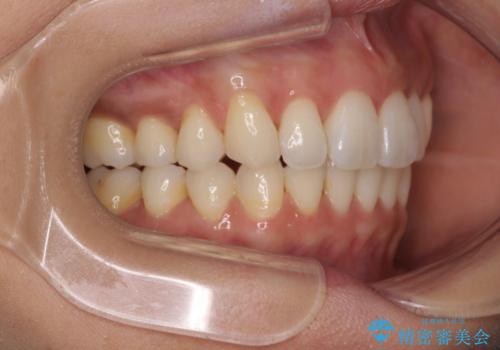

- 前歯の突出感とデコボコを気にして来院された患者様です。

奥歯の噛み合わせをみると、上顎歯列が全体的に前突している状態であり、この咬み合わせのまま歯列を整えると出っ歯になってしまう可能性がありました。

アンカースクリューと補助装置を使用して上顎大臼歯を遠心移動させることで咬み合わせを改善し、ワイヤー装置によりデコボコを解消しながら口元の突出感も改善していくこととしました。

出っ歯になることなく、上下前歯が綺麗に接触する状態で仕上げることができました。